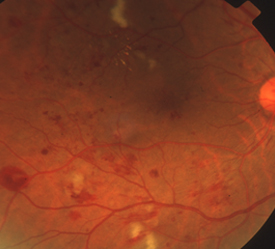

血管の所々に障害が現れ始め、毛細血管瘤、点状・斑状出血、硬性白斑などが現れます。

血管が詰まって、網膜の一部に血液が流れていない虚血部分が生じてきた段階で、そのまま放置すれば次の増殖網膜症に進行します。軟性白斑、血管閉塞、静脈異常、網膜浮腫などが起きてきます。

虚血部分に酸素や栄養を送り込もうと、新生血管が網膜の表面や硝子体に伸びてきます。薄い膜状の増殖膜が形成されたり、新生血管が破れることで硝子体出血、増殖膜が網膜を牽引することで網膜剥離が生じます。